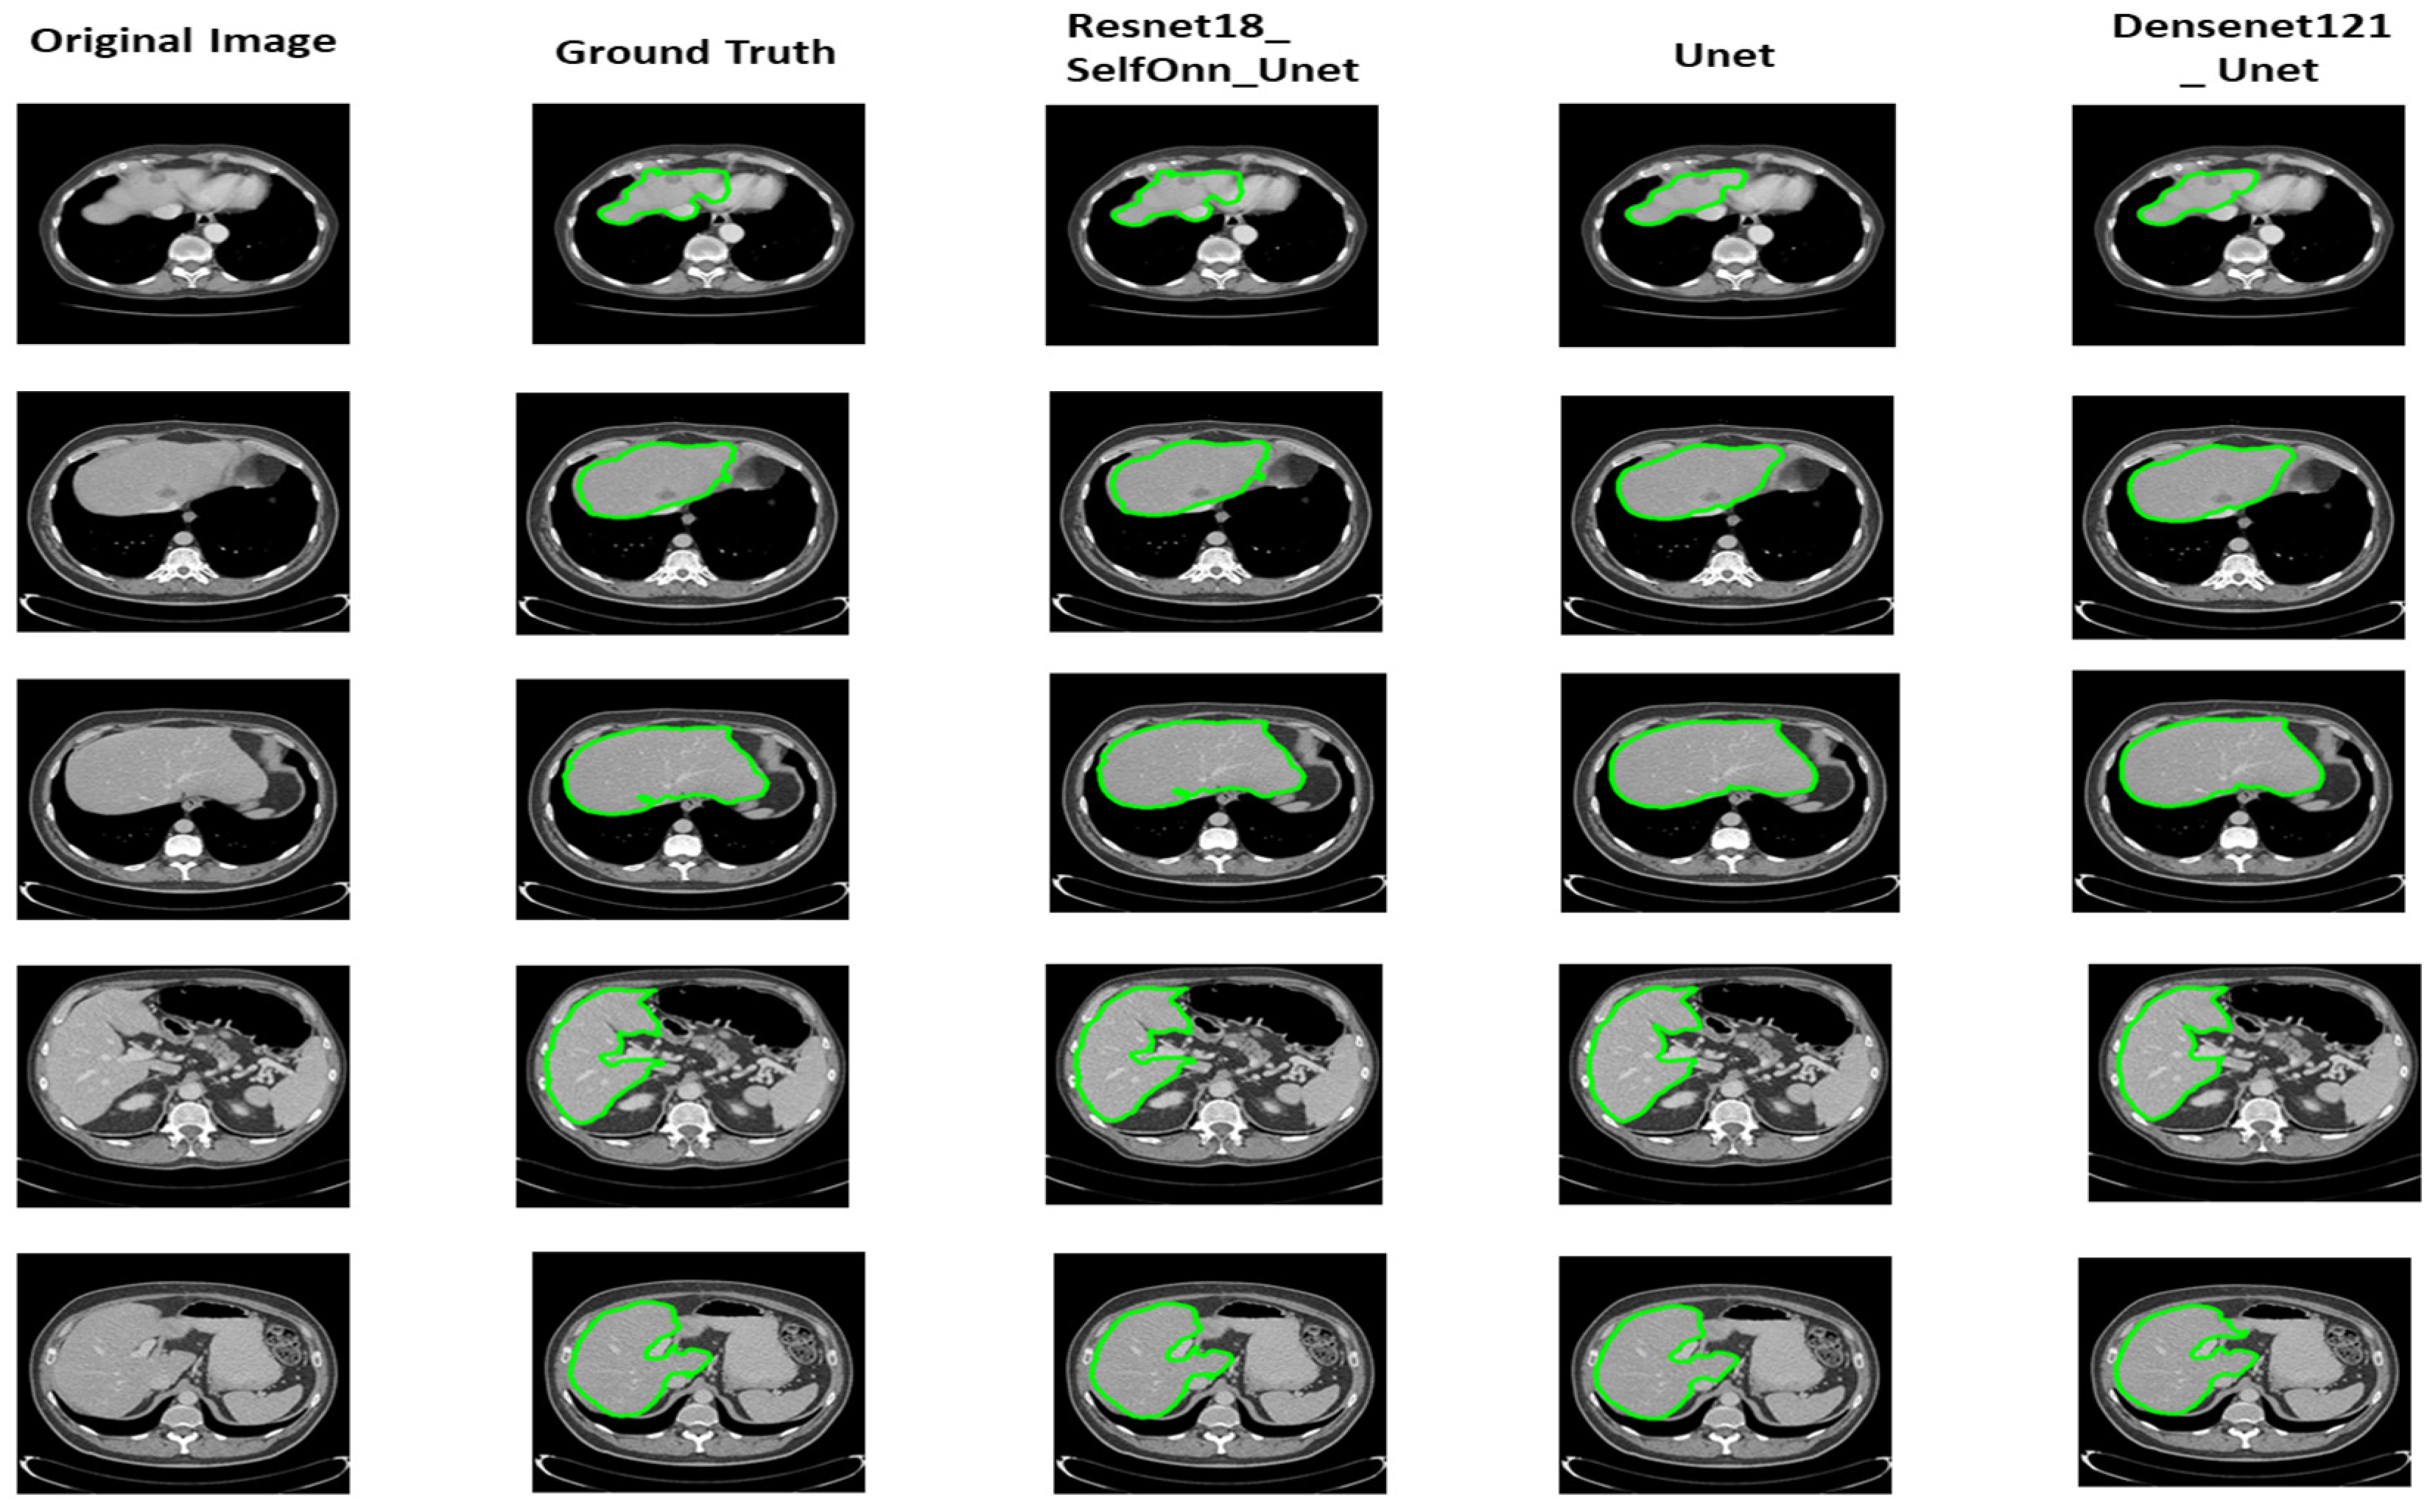

The quantitative results for liver segmentation have been given in Table 3 whereas Figure 5 shows the liver boundary segmented by the best three models with corresponding original and ground truth images. To segment the liver from volumetric CT images, different DenseNet and ResNet backbones were used in conjunction with U-Net, U-Net++, Self-ONN and FPN architectures. Among the results obtained for these networks, it is observed that the ResNet18_Self-ONN_U-Net, vanilla U-Net, and U-Net with DenseNet121 encoder performed the best, achieving dice similarity coefficients (DSCs) of 98.182%, 97.606%, and 97.344%, respectively.

As can be seen from Table 3, the vanilla U-Net network also achieved remarkable performance with a dice similarity coefficient (DSC) of 97.606%. It can be observed from the qualitative assessment that the liver mask produced by ResNet18_Self-ONN_U-Net, U-Net, and DenseNet121 with U-Net is highly consistent with the ground truth. The first column of Figure 4 displays the original CT slice, the second column contains the ground truth mask, and the third, fourth, and fifth columns have the predicted masks from the three most effective models for liver segmentation. The ground truth as well as predicted masks have overlapped over original images, which is further highlighted with a green boundary in order to show more clarity. It can be seen from the segmentation masks that the vanilla U-Net network has produced segmentation masks, even for a small region of the liver. U-Net with a DenseNet121 encoder and U-Net++ with a ResNet18 encoder, the other two high-performance networks, have also segmented the liver into small areas, achieving the highest level of accuracy.

The results of tumor segmentation for the three best models have been shown in Figure 6 with the original liver and ground truth lesion mask annotated by medical experts. It can be seen from the results that U-Net++ has segmented small tumors within the liver as compared to the other two best-performing networks that have missed some of the tumors to be segmented.

Figure 6 shows the performance comparison of different tumor segmentation networks, where the red boundary represents the predicted pixels. Figure 7 and Figure 8 show the mask overlay of ground truth and the predicted mask of the liver and tumor for the samples. The second rows in Figure 7 and Figure 8 show the regions highlighted with red and green boundaries. These borders indicate the incorrect interpretations of the models in the case of liver and tumor prediction. The green boundaries indicate the actual liver and tumor locations in the image, while the red boundaries highlight the model-predicted liver and tumor regions. As a result, this misinterpretation of the models, which predicted the incorrect liver and tumor locations, did not contribute to the dice score, affecting the overall dice score for both the liver and tumor.

Figure 5. The columns from left to right show the comparison of different liver segmentation networks. The first column shows the original images, followed by the ground truth images. The outcomes of the top three performance networks with the highest dice scores are shown in the remaining three columns. The liver in the ground truth and the segmented images has been highlighted with a green boundary.

Figure 6. Performance comparison of different tumor segmentation networks(the red boundary shows the predicted pixels).